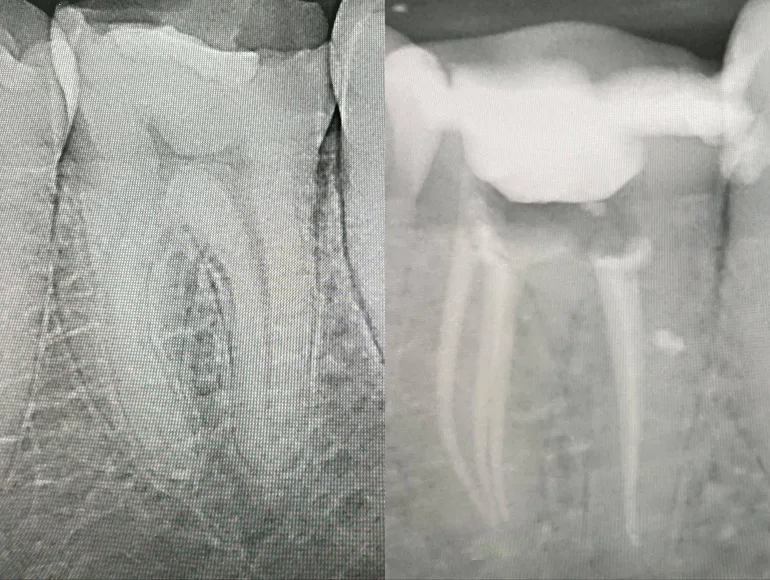

Extreme Curved Roots

Case by Dr. Taha Azimaie: Rootcanal treatment in extreme curved roots is technique sensitive procedure and require skills and right equipments.